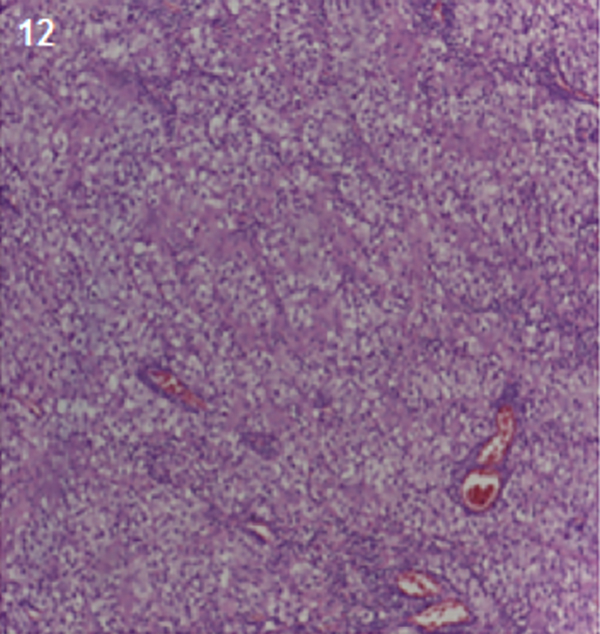

Para el análisis anátomo-patológico, se enviaron múltiples fragmentos irregulares de tejido que medían de entre 3,8 cm y 0,5 cm de diámetro máximo, los cuales revelaron al examen microscópico una proliferación de células neoplásicas de estirpe germinativo constituida por dos componentes: uno de ellos caracterizado por células con núcleos redondos, hipercromáticos, ligeramente irregulares con citoplasmas claros y amplios dispuestos en nidos sólidos, surcados por finos ejes fibroconectivos vascularizados con presencia de acúmulos linfocitarios; el segundo componente presentaba elementos teratomatosos maduros, en sectores inmaduros, derivados principalmente de la capa mesodérmica y endodérmica. A nivel de esta última se destacaban características atípicas y áreas necrohemorrágicas.

En base a los hallazgos antes descriptos se arribó al diagnóstico de Neoplasia de células germinales mixtas: Germinoma (35%) y Teratoma con áreas Inmaduras y transformación carcinomatosa (65%),(Figura 11 y 12).

Figura 12: Germinoma